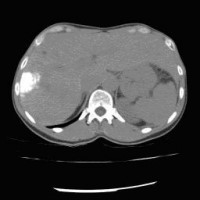

Computertomographische Dokumentation der Embolisateinlagerung innerhalb des Tumors nach transarterieller Chemoembolisation (TACE)

(Bild 2 von 5)